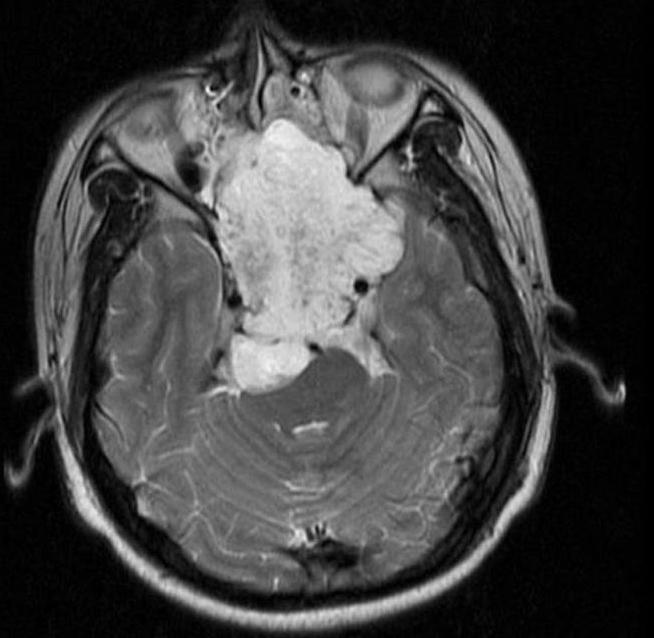

Esthésioneuroblastome

L’esthesioneuroblastome, également connu sous le nom de neuroblastome olfactif, est un cancer rare qui se manifeste dans le bulbe olfactive, la partie du cerveau qui interprète l’odeur. Les symptômes varient en fonction de l’emplacement et de l’étendue de la tumeur. Les symptômes les plus courants sont l’obstruction nasale, les saignements de nez, les maux de tête, les douleurs faciales et la diminution de l’odorat.

Les esthésioneuroblastomes sont traités chirurgicalement par chirurgie endoscopique endonasale et peuvent être suivis d’une radiothérapie ou d’une chimiothérapie.